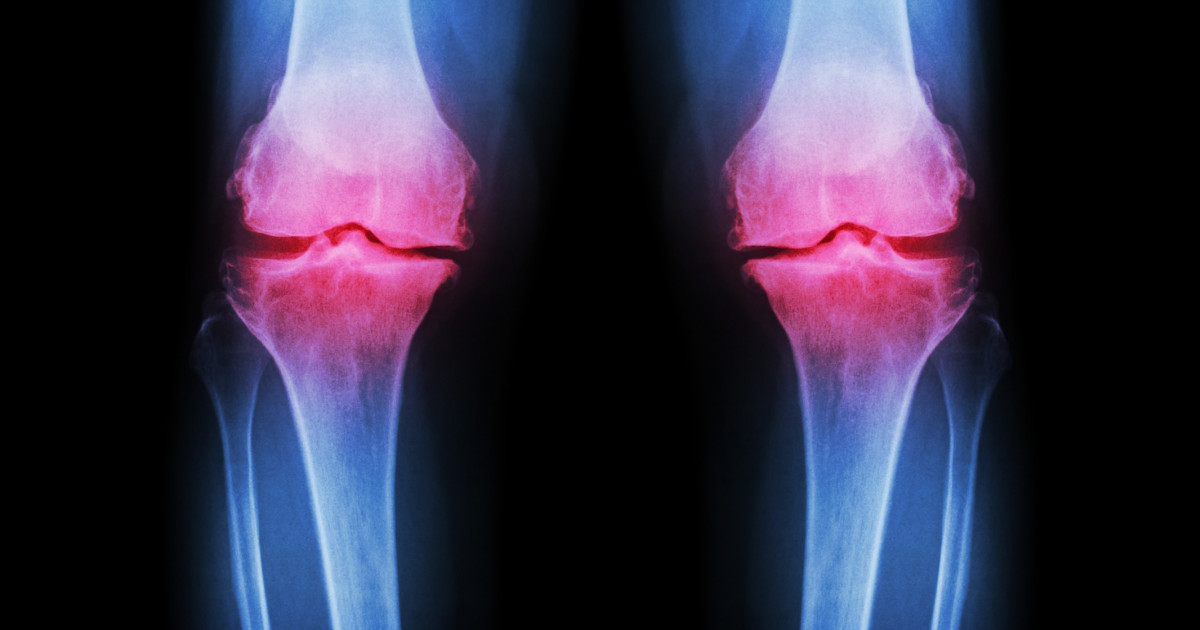

Osteoarthritis

Osteoarthritis is just one of several conditions that can increase an individual's risk of developing septic arthritis. When a patient already has problems with their joints, the joints are more susceptible to infection due to weakness and prior damage. Chronic joint conditions like osteoarthritis, lupus, and gout are often seen alongside septic arthritis cases. Osteoarthritis most commonly affects the joints in an individual's spine, hips, hands, and knees, though it is possible for any joint to be affected. Typically, symptoms include joint stiffness, pain, and tenderness, as well as a grating sensation when the affected joint is used, a loss of flexibility in the joint, as well as bone spurs. It is crucial for osteoarthritis patients to receive appropriate and prompt treatment in order to mitigate the potential for septic arthritis to develop.